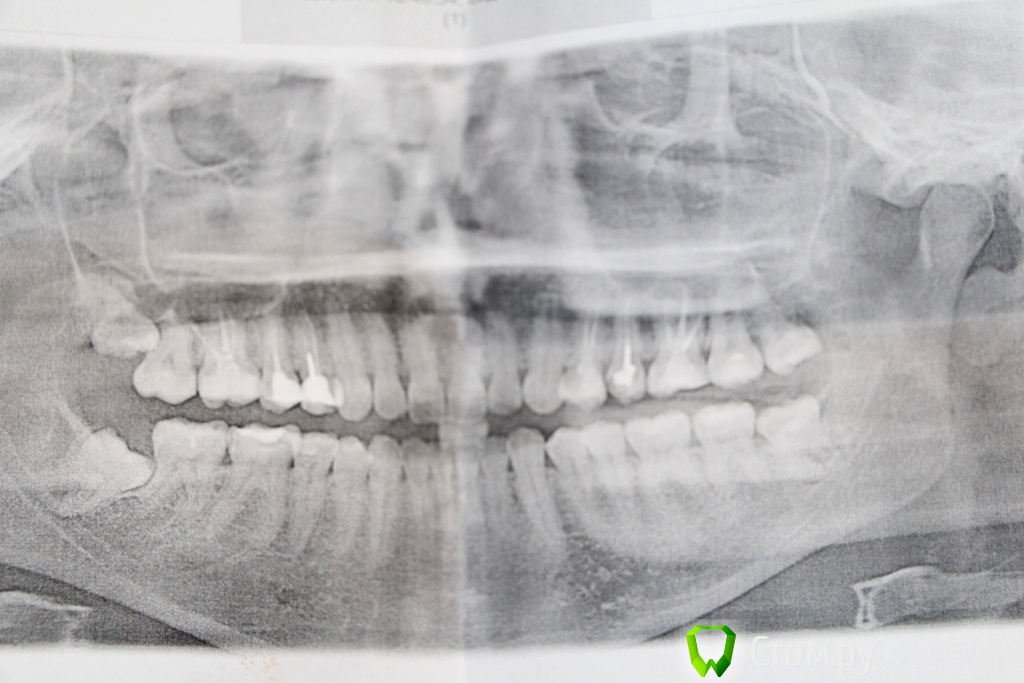

vichka.vika.13 Опубликовано 9 сентября, 2014 Поделиться Опубликовано 9 сентября, 2014 Мне удалили верхний и нижний зуб мудрости, с левой стороны, на снимке видно, что они более меня правильно выросли, но верхний быстро начал разрушаться, а нижний давил на семерку. Верхний без проблем удалили, нижний сложнее, резали, но тоже терпимо. А вот с правой стороны зубы мудрости ретинированные, и верхний, и нижний, полубоком, упираются в корни семерок. Их точно надо будет удалять. Но дело в том, что они еще даже не показались из десны и не болят. У врача спросила, ждать, когда полезут. она вроде как да, но толком ничего не сказала. Только, что удалять надо будет. Вот и непонятно, когда они прорежутся? сколько времени может пройти? Или можно удалить прям из десны, непрорезавшиеся? И кто удалял такие зубы, ретированные, примерно, как у меня на снимке? Очень тяжелое удаление? Спасибо! И вы ждали, когда прорежутся сначала? Ссылка на комментарий